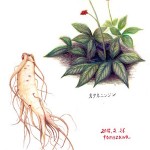

人参

ウコギ科のオタネニンジンの根。

性味:甘・微温・微苦

帰経:肺・脾

主な薬効と応用

①補気固脱:大病・久病・大出血・激しい嘔吐などで

元気が虚衰して生じるショック状態時に用いる。

方剤例⇒独参湯

②補脾気:脾気虚による元気がない・疲れやすい・食欲不振、

四肢無力・泥状~水様便などの症候時に用いる。

方剤例⇒四君子湯

③益肺気:肺気虚による呼吸困難・咳嗽・息切れ(動くと増悪する)・自汗などの症候時に用いる。

方剤例⇒人参胡桃湯

④生津止渇:熱盛の気津両傷で高熱・口渇・多汗・元気がない・脈が大で無力などの症候時に用いる。

方剤例⇒白虎加人参湯

⑤安神益智:気血不足による心身不安の不眠・動悸・健忘・不安感などの症候時に用いる。

方剤例⇒帰脾湯

備考:生化の源である脾気と一身の気を主る肺気を充盈することにより一身の気を旺盛にし、

大補元気の効能をもつ。すべての大病・久病・大出血・大吐瀉による元気虚衰の

虚極欲脱・脈微欲脱に対して最も主要な薬物。